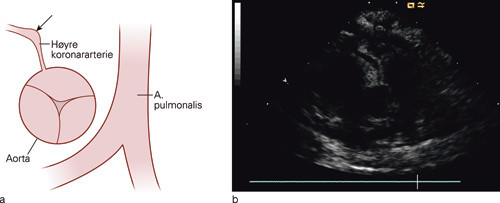

Man hadde observert barnet i fem dager med vedvarende høy feber, diaré, cervikal lymfadenopati (en forstørret lymfeknute på halsen) og konjunktivitt. Det var ingen sikre funn fra den foreløpige utredningen, og barnets tilstand var fremdeles uavklart. CRP var på 150 – 200 mg/l og trombocyttkonsentrasjonen var steget til 644 x 10⁹. På dette tidspunktet var det aktuelt å tenke på andre inflammatoriske tilstander som differensialdiagnoser. Selv om han kun innfridde to av fem kriterier for Kawasakis sykdom, ble gutten henvist til ekkokardiografi med tanke på inkomplett Kawasakis sykdom. EKG var normalt. Ved ekkokardiografi fant vi signifikant dilatasjon av begge koronararterier og noe perikardvæske. På grunn av de karakteristiske dilaterte koronararteriene ble det konkludert med at barnet hadde en inkomplett, neonatal Kawasakis sykdom. Barnet fikk immunglobulin intravenøst 2 g/kg som engangsdose og acetylsalisylsyre peroralt 80 mg/kg/døgn. Han ble afebril etter to døgn, og dosen med acetylsalisylsyre ble derfor redusert til 5 mg/kg/døgn som tromboseprofylakse. Ved kontroll to måneder senere var det normale funn ved ekkokardiografisk undersøkelse og barnet var friskt fra sin hjertetilstand.

Når det foreligger feber over fem dager og mindre enn fire kriterier, kalles det inkomplett eller atypisk Kawasakis sykdom. Inkomplett Kawasakis sykdom diagnostiseres oftest etter at det er påvist anomalier på koronarkar. Hos pasientene med denne sykdomsvarianten er det en høy komplikasjonsrate, mest sannsynlig på grunn av forsinket diagnose og behandling. Barn under tre måneders alder utgjør under 2 % av tilfellene med Kawasakis sykdom (6) og er ofte symptomfattige og med atypiske funn (7). I en tidligere norsk studie er det anbefalt å ha lavere terskel for å behandle spedbarn med et ufullstendig bilde (8). Ekkokardiografi er en ikke-invasiv undersøkelse som kan være nyttig i situasjoner med langvarig feber uten kjent årsak. Undersøkelsen kan ikke utelukke Kawasakis sykdom og må gjentas ved sterk klinisk mistanke. I vårt tilfelle ga ekkokardiografisk undersøkelse diagnosen på et tidlig tidspunkt. Man må huske at spedbarn kan få inkomplett Kawasakis sykdom, og da med en spesiell høy risiko for komplikasjoner.